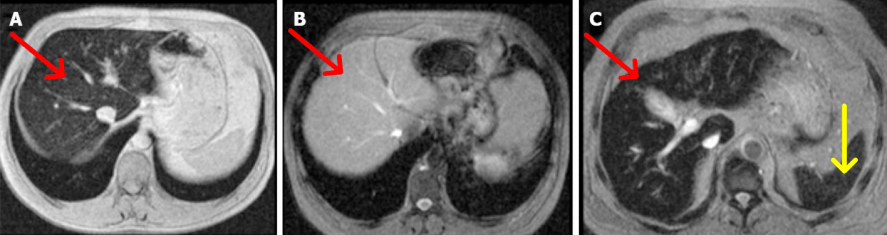

Além da avaliação do fígado, coração, etc, os exames de imagem têm uma função importante na hemocromatose: medir o depósito do ferro nos órgãos. Como o ferro é um metal, é possível realizar exame de ressonância nuclear magnética com quantificação do ferro nos dois órgãos mais afetados, o fígado e o coração. O exame não é perfeito, pode errar no diagnóstico com falso positivo e falso negativo em torno de 80%, mas não é invasivo e ajuda muito a fechar o diagnóstico quando associado aos exames laboratoriais. Uma curiosidade é que a HH não leva a acúmulo de ferro no baço, se isso foi observado deve-se pensar em hemocromatose adquirida ou do tipo 4.

Ressonância nuclear magnética para avaliar depósito de ferro. (A) Fígado mais escuro (seta vermelha), em paciente com hemocromatose hereditária. (B) Fígado de portador de HH após tratamento prolongado com flebotomias, com intensidade normal (seta vermelha). (C) Paciente com hemocromatose adquirida (secundária), com depósito de ferro no fígado (seta vermelha) e no baço (seta amarela). Fonte: Castiella A, Zapata E e Alústiza JM